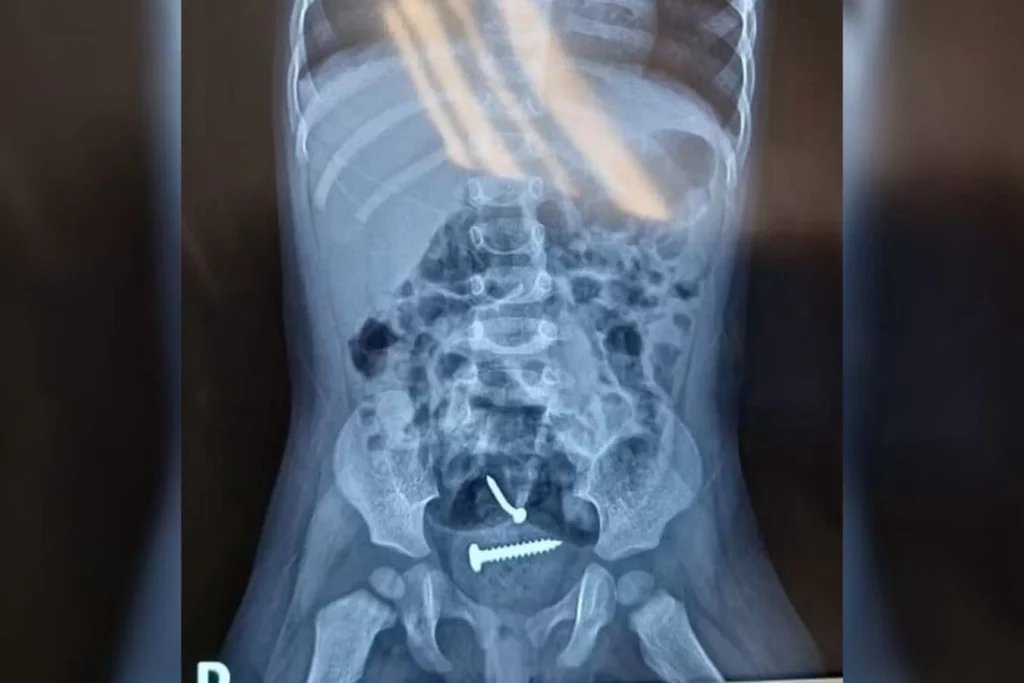

A situação foi denunciada pelo Hospital de Urgência de Teresina, onde as duas vítimas passaram por perícia médica e os resultados foram encaminhados para a delegacia responsável. Além dos objetos estranhos dentro da menina, lesões nas partes íntimas também foram achadas.

Parafusos são encontrados dentro de bebê de 1 ano; pai é suspeito de estuprá-la